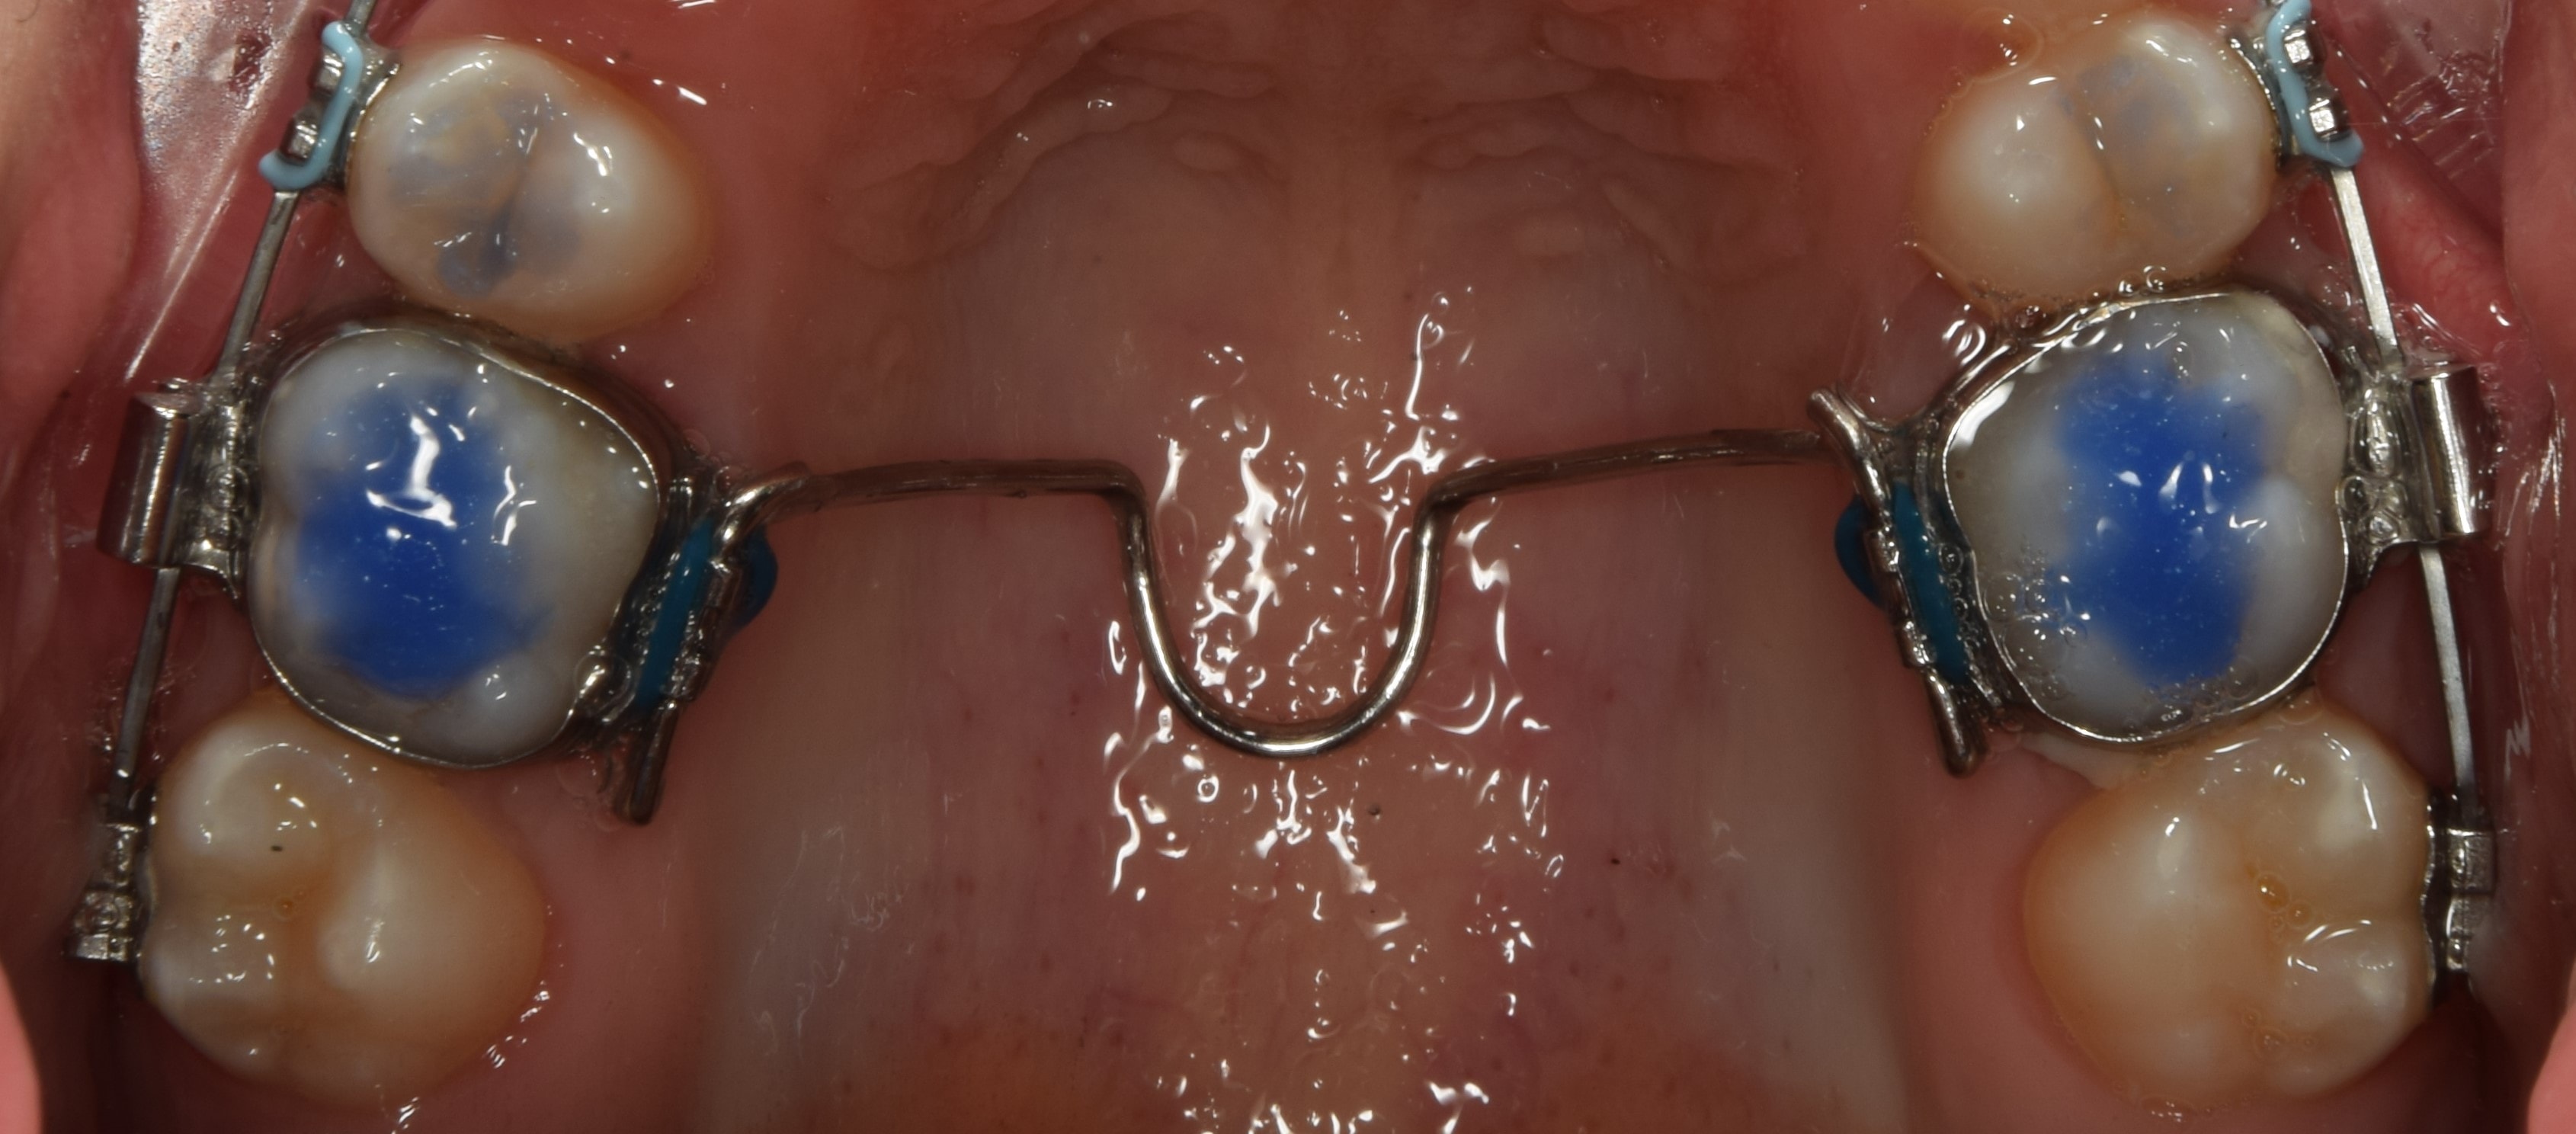

2. Jóval gyakoribb a szájpad különböző területeire behelyezett miniimplantátumok segítségével történő disztalizálás. Végtelen számú készülék van erre a célra, én a TOP JET disztalizálót használom. Ez két darab, a felső szemfog-első kisőrlő szájpadi oldalára betekert miniimplantátumból, két darab rugós teleszkópból, valamint egy a felső első őrlőfogakon gyűrűvel rögzülő, szájpadot áthidaló acélívből áll. Előnye, hogy a szájpad ezen részén nagyon megbízható, kiváló minőségű csontállomány található, a kezelés kiszámítható, illetve egyedülálló tulajdonsága, hogy nincs szükség fogtechnika bevonására (legfeljebb a szájpadív+gyűrű elkészítésére, de a készülék maga előregyártott, egyszerűen adaptálható). Hátránya, hogy igen drága. Sikerességi rátája 95% fölötti.